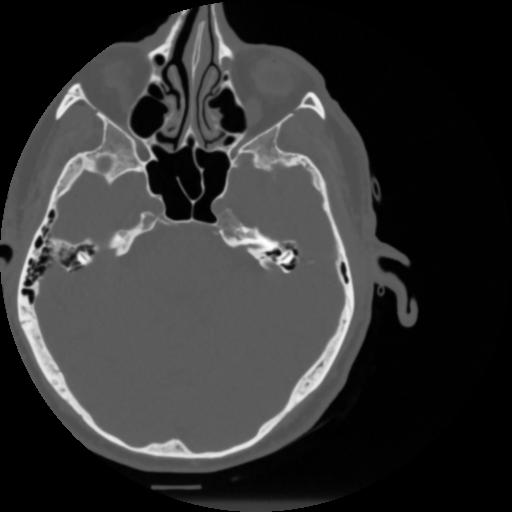

4 CEREBRO,,Vol,0.5,CEREBRO,,